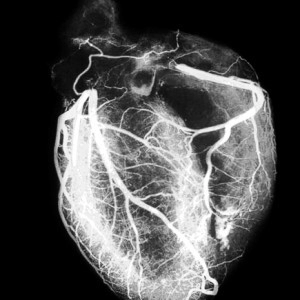

В случаях, когда необходимо получить подробную и точную информацию о состоянии тканей и сосудов сердца, используется метод магнитно-резонансной томографии. МРТ сердца является неинвазивной процедурой, т. е. выполняемой без нарушения целостности тканей. Обработка полученной информации при помощи компьютера позволяет визуализировать сердечную мышцу и сосуды в различных ракурсах, а также оценивать скорость и объем кровотока, другие функциональные особенности органа. Для исследования не используется рентгеновское излучение, поэтому процедура практически полностью безвредна.

Исследование позволяет оценить состояние сердечной мышцы, коронарных сосудов, клапанов, желудочков и других элементов, причем не в неподвижном состоянии, а во всех фазах цикла сокращений. Одновременно оцениваются параметры кровотока, выявляются повреждения и патологические изменения сосудов. Возможен прогноз инфаркта и выявление повреждений при постинфарктных состояниях.